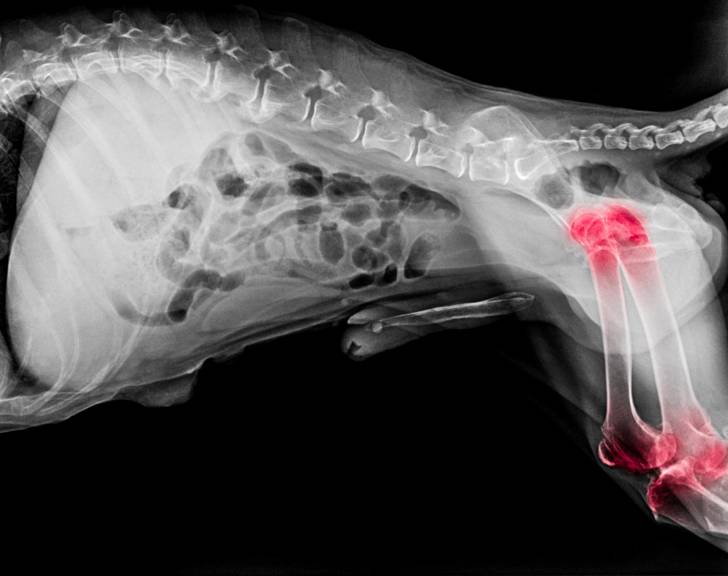

La méthode OFA consiste à faire s'allonger le chien de dos sur une table et à effectuer une radiographie de ses hanches. À partir de ce cliché, il est possible d'évaluer l'état de l'articulation, de déterminer s'il y a déjà de l'arthrose et de mesurer l'angle dit de Norberg-Olsson, formé par la droite joignant les centres des deux têtes fémorales et la droite joignant le centre de la tête fémorale au bord crânio-acétubulaire.

Une note est ensuite déterminée pour chaque hanche, à partir des observations effectuées :

| Angle | Etat de l'articulation | Note |

|---|---|---|

| Supérieur à 105° | Hanche parfaite ou quasi parfaite | A |

| Entre 100 et 105° | Légère déformation de la tête du fémur et léger aplatissement de l'acétabulum | B |

| Entre 90 et 100 ° | Acétabulum déformé et arthrose légère | C |

| Inférieur à 90° | Acétabulum déformé et arthrose modérée | D |

| Inférieur à 90° | Luxation articulaire de la hanche et arthrose sévère | E |

Plus la note est basse, plus la dysplasie est sévère.